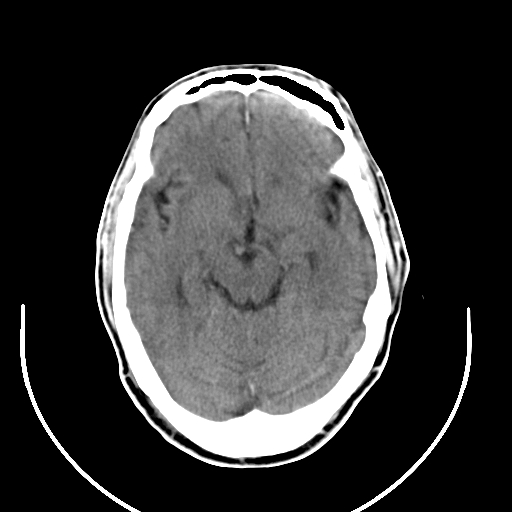

以下是引用zjzjr在2008-7-26 10:37:00的发言:[br]钙化性脑膜瘤

以下是引用朱亮在2008-7-26 10:32:00的发言:[br]钙化性脑膜瘤

以下是引用拾荒者在2008-7-26 15:36:00的发言:[br]侧脑室内高密度钙化影,未见软组织结构,侧脑室未见增大,考虑良性钙化性改变(钙化型脑膜瘤可能)。